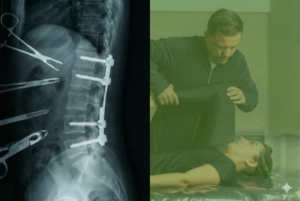

O principal exame é o Raio-X da coluna total em pé, que permite medir o Ângulo de Cobb, responsável por classificar a gravidade da escoliose:

- Até 10°: assimetria postural

- 10° a 25°: escoliose leve

- 25° a 40°: escoliose moderada

- Acima de 40°: escoliose severa

Em casos específicos, pode ser solicitada ressonância magnética.

Tratamento para Escoliose Sem Cirurgia na Clínica Coluna SP

Aqui está a parte mais importante: é possível tratar a escoliose sem cirurgia.

O Protocolo Coluna Sem Dor para Escoliose combina os métodos mais eficazes da fisioterapia moderna, com foco em exercícios ativos e personalizados.